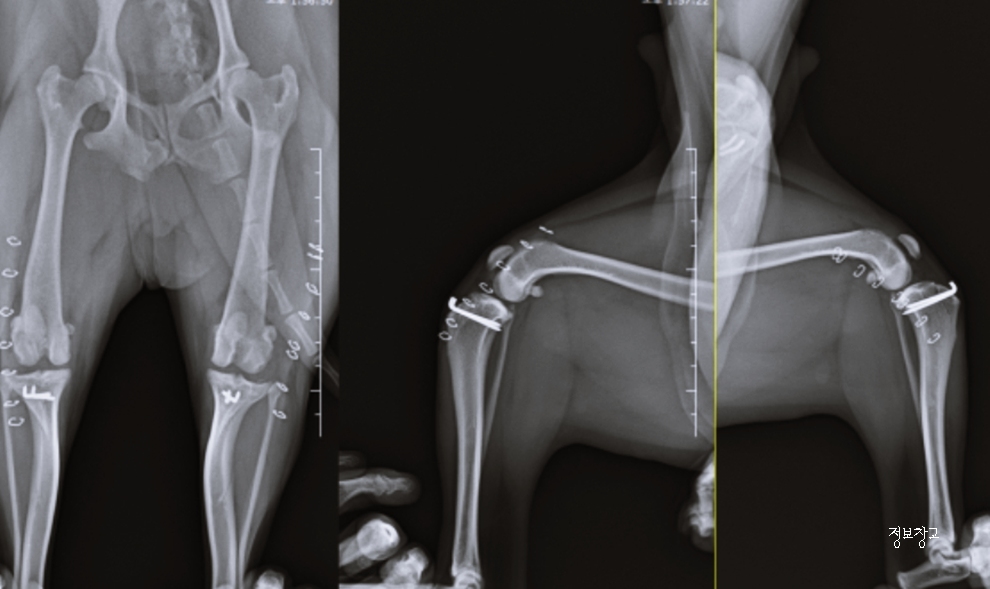

- 슬개골 탈구

2. 슬개골 탈구란 무엇인가요?

슬개골 탈구는 무릎뼈(슬개골)가 정상 위치에서 벗어나는 질환으로,

특히 소형견에게 매우 흔한 질환입니다.

7. 슬개골 탈구, 방치하면 어떻게 될까요?

초기에는 가볍게 보일 수 있지만

방치 시 다음과 같은 문제로 이어질 수 있습니다.

- 만성 관절염

- 다리 변형

- 보행 장애

- 수술 필요 가능성 증가